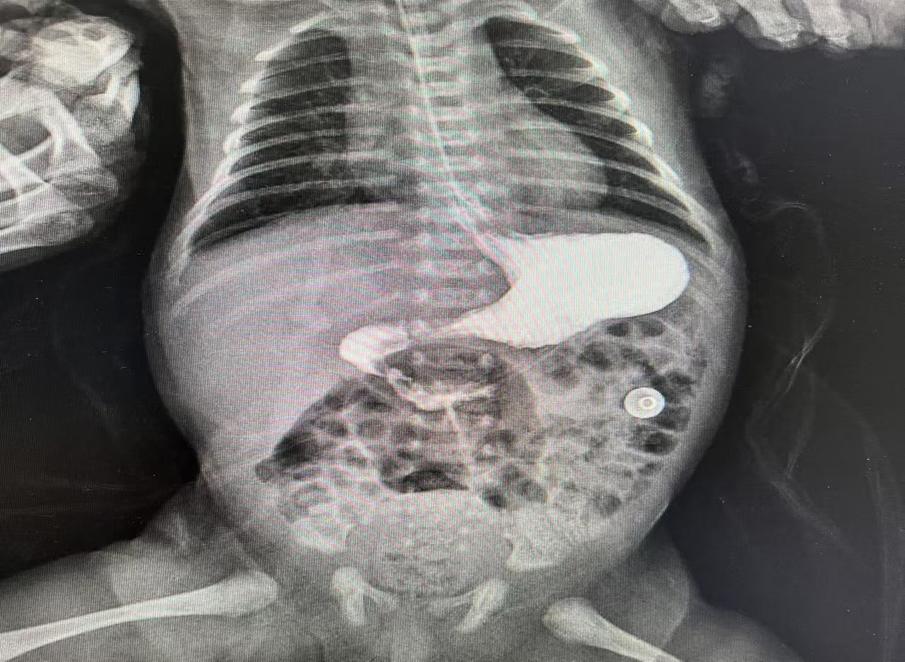

圖片7.jpg

術(shù)前造影提示十二指腸遠(yuǎn)端閉鎖